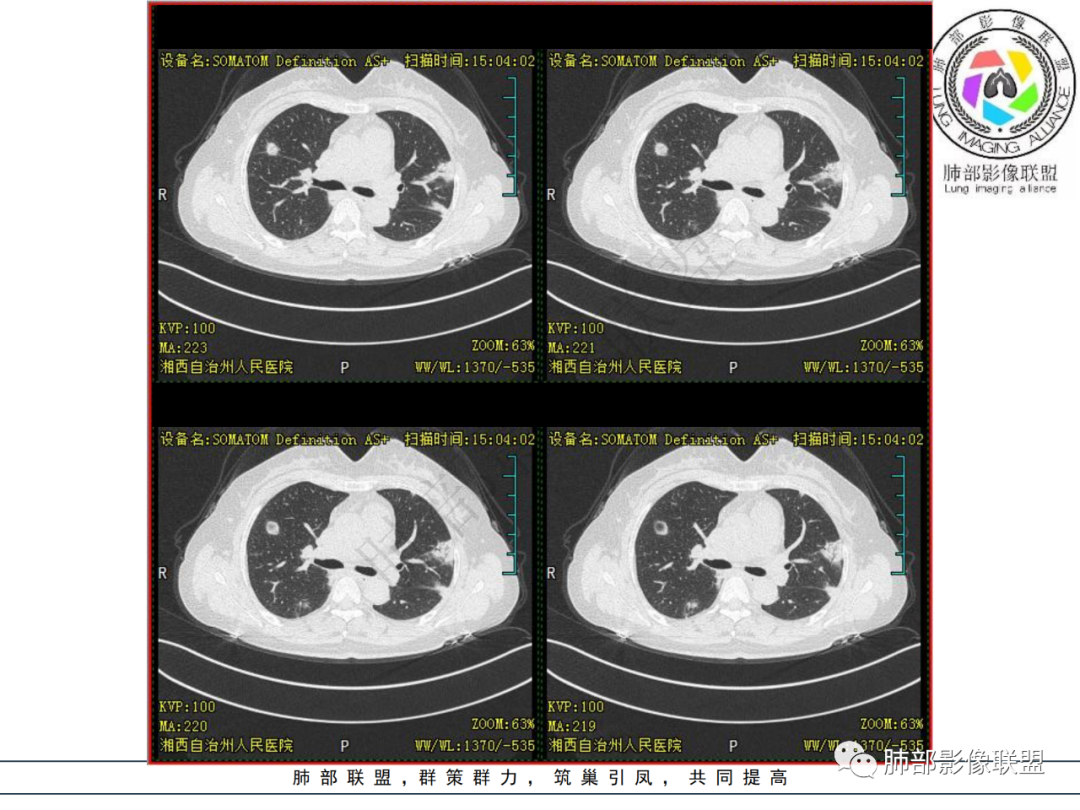

中年妇女,类风湿性关节炎病史,RF升高,感染性指标正常,双肺散在多发结节、斑片、条片灶,边缘欠清晰,大部分胸膜下分布,部分反晕,考虑RA-ⅠLD ,OP样改变

中年女性,有类风湿关节炎病史,双肺内及胸膜下见多发结节,条索状及小实变影,部分结节病灶垂直支气管血管束生长,部分结节病灶内见偏心性空洞形成,病灶收缩力弱,病灶形态多样,部分可见纤维化样改变,整体符合Op表现,结合患者病史,考虑类风湿结节,隐球菌感染不能排除。

中年女性,类风湿关节炎病史,双肺散在结节影,胸膜下分布为主,部分可见小空洞影,部分可见索条影,OP样改变,考虑类风湿结节,鉴别隐球菌

双肺散在多发结节及斑片,边缘欠清晰,胸膜下分布为主,部分内可见支气管扩张,妇女,类风湿性关节炎病史,RF升高,感染性指标正常,考虑RA-ILD,鉴别淋巴瘤。

双肺多发斑片影、结节影,胸膜下分布为主,部分沿支气管血管束分布,病灶大部分边缘平直。

双肺多发结节状及斑片状不均质磨玻璃病灶,胸膜下分布为主,边缘有收缩、凹陷,部分反晕,病灶内可见支气管扩张。中年女性,类风湿关节炎,感染指标正常。类风湿结节?隐球菌?

女,49岁,类风湿因子升高,影像双肺斑片及小结节影,胸膜下分布为主,部分病灶内支气管扩张,双侧胸膜增厚,复查病灶增多增大,考虑RA_ILD。

女性,49岁,多关节肿痛1年余。RF升高。胸部CT:双肺多发斑片影、结节影,胸膜下为主,部分沿支气管血管束分布,大小不等,部分病灶内支气管扩张,部分呈反晕,部分呈楔形宽基底贴附胸膜,复查CT进展,考虑:CTD—ILD?OP?鉴别血管炎、HP、肺梗、曲霉等。

中年女性,多关节肿痛一年,类风湿因子增高,双肺及胸膜下可见多发大小不一结节,部分呈楔形,以胸膜下分布为主,边缘平直,部分病灶分布于支气管血管束,部分可见空气支气管征、反晕征,复查病灶进展,类风湿结节?OP?

胸部CT提示双肺多发的斑片实变结节影,磨玻璃。病灶分布以双肺胸膜下为主,部分病灶以支气管血管素分布,病灶内可见支气管穿行。总体符合间质性肺疾病。

双肺多发结节,胸膜下为主,内见空洞,边缘模糊见毛刺。类似病灶可见于:肺结核、肺隐球菌病、SPE、血管炎、类风湿结节……无发热、白细胞计数不高,排除SPE;无发热、消瘦、盗汗等症状,病灶形态较单一、无树芽征,肺结核可能性小;无多系统损害,GPA可能性小;肺内病灶较多,无明显临床症状,隐球菌抗原阴性,肺隐球菌病可能性小。结合病史,考虑类风湿结节可能性大。鉴别隐球菌病、肺结核。

2.双肺多发片状影,胸膜下分布为主,部分沿支气管血管束分布,边界不清,实性及磨玻璃密度,趋于柔和,可见支气管进入或穿行,未见空洞、钙化及树芽等。部分病灶显示反晕。